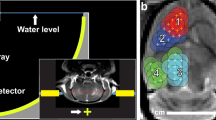

Through the combination of a marmoset-specific atlas (cytoarchitectonic boundaries registered24 to MRI space25,26) and a now commercially available marmoset-specific focused ultrasound apparatus (Fig. 1; RK-50 Marmoset, FUS Instruments Incorporated, Toronto, ON, Canada), we demonstrate the requisite parameters to reliably stereotactically target and open the BBB to a small parenchymal volume (~10–20 mm3) with a single element 1.46 MHz transducer. We demonstrate the effects of center frequency on BBB disruption size, acoustic attenuation due the marmoset skull, the minimum acoustic pressure to disrupt the BBB, and the deleterious effects of too much acoustic pressure. We also demonstrate the minimum microbubble dosage for BBB disruption at safe acoustic pressure, estimate microbubble clearance time, and the effect of skull angle on BBB disruption. Through reporting by in vivo gadolinium-enhanced MRI and ex vivo Evans Blue staining as well as histological and immunohistochemical reporting, we provide a detailed account of the requisite parameters for safely, reproducibly, and focally disrupting the BBB in the common marmoset.

a Computer-aided design three-dimensional rendering of the stereotactic positioning of the marmoset with reference to the transducer and hydrophone. b Software MORPHEUS (FUS Instruments, Toronto, Ontario, Canada) with our marmoset atlases integrated along with cytoarchitectonic boundaries. c Relative size of BBB disruption using 515 kHz and 1.46 MHz transducer overlayed on marmoset atlas. d Relative size of BBB disruption as reported by Evans blue staining in Marmoset B.

Marmoset B received two sonications in parietal cortex to determine the relative difference in BBB disruption size as a function of transducer center frequency. With the goal of minimizing the size of disruption, both transducers (515 kHz, left hemisphere; 1.46 MHz, right hemisphere) were focused on the edge of the cortex (Fig. 1c)—consequently, only about half of the ultrasonic beam in the axial orientation was focused on brain tissue. As evidenced by the Evans blue staining (Fig. 1d), both sonications were close in volume to the full width at half maximum of the acoustic pressure distribution at the focus (with 515 kHz at 188 mm3 and 1.46 MHz at 10 mm3). With the aim of subsequent experiments to demonstrate focal BBB disruptions, only the higher-frequency 1.46 MHz transducer was used. As reliably demonstrated across the experiments described below, the method of centering the focus of the 1.46 MHz transducer at the top of the cortex allowed for disruptions on the order of 1 mm radially, and 2.5 mm axially. Indeed, the disruption size varied slightly as a function of acoustic pressure, microbubble dosage, burst duration, and number of bursts, but at the “safe” parameters demonstrated below, the 1.46 MHz transducer allowed for cortical disruptions within the bounds of most cortical cytoarchitectonic regions of interest (e.g., fit within the medial-lateral extent of area MIP).

BBB disruption as a function of center frequency

Marmoset B received two sonications in parietal cortices to determine the relative difference in BBB disruption size as a function of transducer center frequency (Fig. 1c). With previous reports of reliable BBB disruption in rats (who have a similar skull thickness and brain size to marmosets) at ~500 kHz and its harmonic ~1.5 MHz29 we tested both a 515 kHz and 1.46 MHz transducer, but as we go on to show, the size of opening from 1.46 MHz was more suitable for the experiments described in this study and thus all other sonications were performed at 1.46 MHz. The only sonication performed at 515 kHz was in left parietal cortex of Marmoset B (1 MPa commanded, derated ~0.5 MPa), 30 ms burst duration, 1000 ms burst period, 90 bursts, 400 μl/kg microbubble dose). Right parietal cortex in the same animal was sonicated with a 1.46 MHz transducer (1.70 MPa (derated), 30 ms burst duration, 1000 ms burst period, 90 bursts, 400 μl/kg microbubble dose). BBB disruption was reported by Evans blue staining ex vivo.